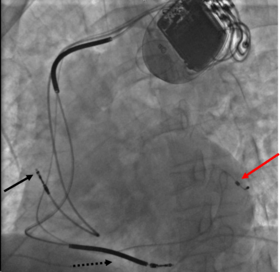

Three leads can be seen in this example of a cardiac resynchronization device: a right atrial lead (solid black arrow), a right ventricular lead (dashed black arrow), and a coronary sinus lead (red arrow). The coronary sinus lead wraps around the outside of the left ventricle, enabling pacing of the left ventricle. Note that the right ventricular lead in this case has 2 thickened aspects that represent conduction coils and that the generator is larger than typical pacemaker generators, demonstrating that this device is both a pacemaker and a cardioverter-defibrillator, capable of delivering electrical shocks for dangerously fast abnormal ventricular rhythms.

Cardiac resynchronization therapy (CRT) is used for people with heart failure in whom the left and right ventricles do not contract simultaneously (ventricular dyssynchrony), which occurs in approximately 25–50% of heart failure patients. To achieve CRT, a biventricular pacemaker (BVP) is used, which can pace both the septal and lateral walls of the left ventricle. By pacing both sides of the left ventricle, the pacemaker can resynchronize the ventricular contractions.

CRT devices have at least two leads, one passing through the vena cava and the right atrium into the right ventricle to stimulate the septum, and another passing through the vena cava and the right atrium and inserted through the coronary sinus to pace the epicardial wall of the left ventricle. Often, for patients in normal sinus rhythm, there is also a lead in the right atrium to facilitate synchrony with the atrial contraction. Thus, timing between the atrial and ventricular contractions, as well as between the septal and lateral walls of the left ventricle can be adjusted to achieve optimal cardiac function.